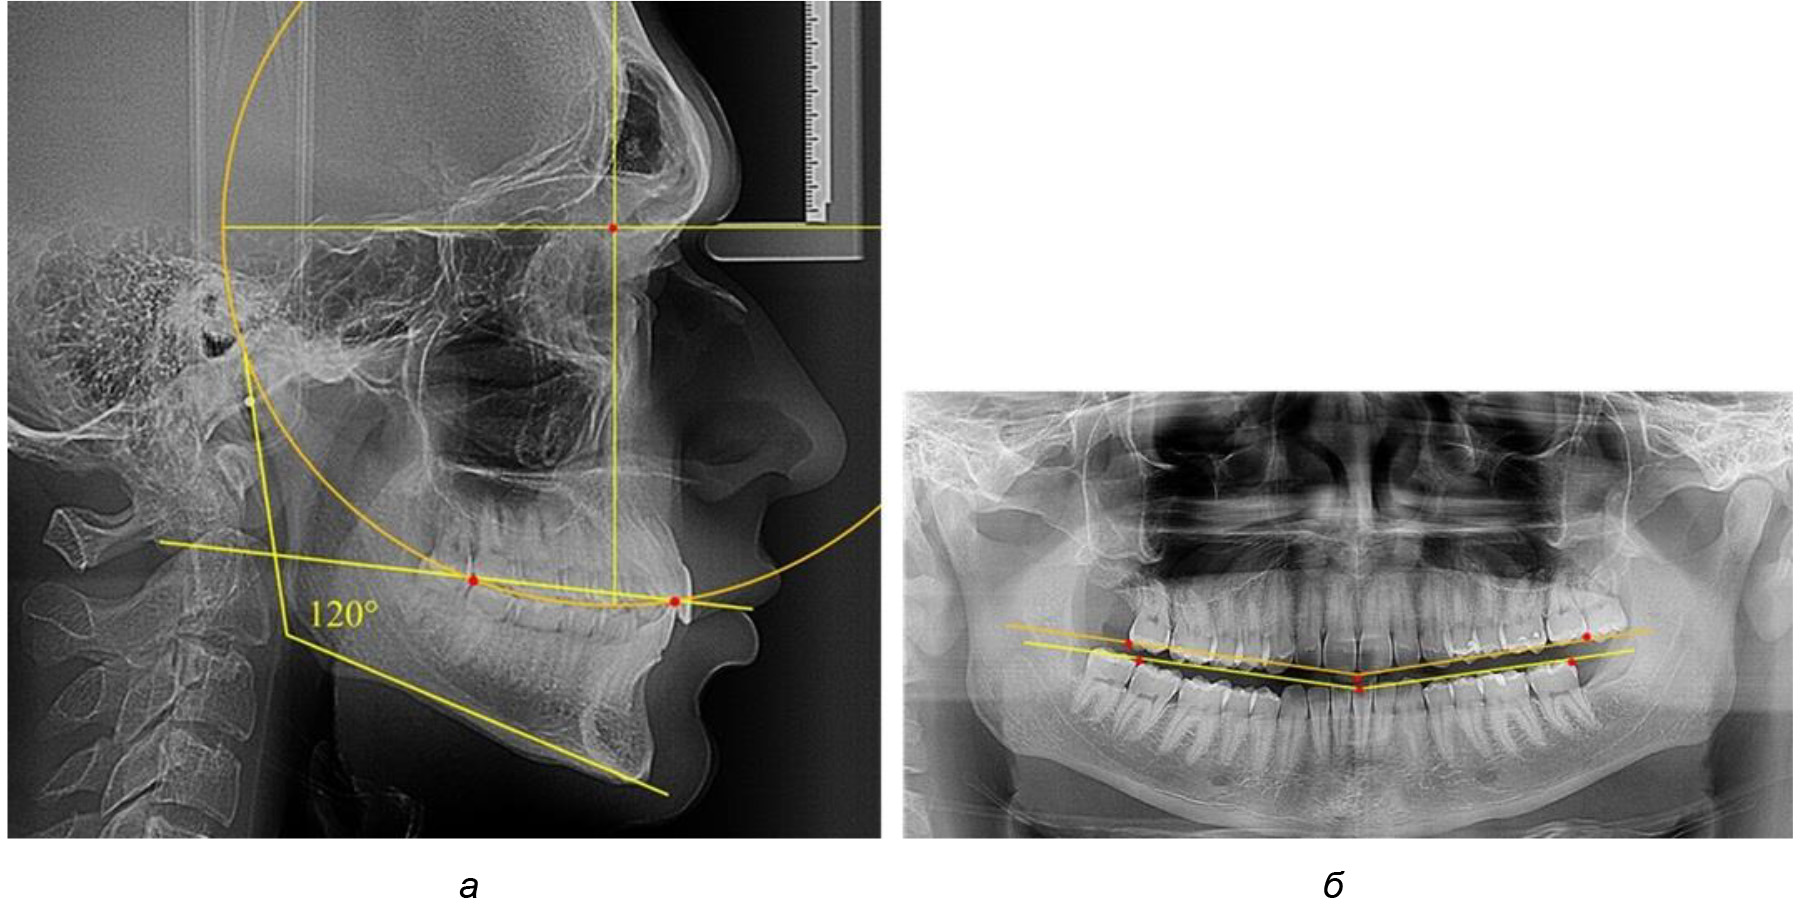

При анализе латеральных ТРГ устанавливали реперный окклюзионные точки в переднем и боковом отделе. Передняя точка устанавливалась на режущем крае нижнего медиального резца, которую в клинике ортодонтии обозначают как vPOcP. Дистальная точка второго нижнего моляра обозначалась как hPOcP. Измеряли расстояние между окклюзионными точками, что определяло сагиттальный размер окклюзионной линии. Использование программ PowerPoint позволило проводить окружность, проходящую по линии смыкания зубов через окклюзионные точки. Измеряли радиус окружности. Учитывая вариабельность размеров окклюзионной линии и радиуса окружности, определяли относительный показатель через отношение радиуса круга к длине сагиттального размера окклюзионной линии. Глубину окклюзионной кривой измеряли от точки наибольшей выпуклости до окклюзионной линии (рис. 1). На ортопантомограмме (ОПТГ) также соединяли окклюзионные точки правой и левой стороны и измеряли глубину окклюзионной кривой от точки наибольшей выпуклости до окклюзионной прямой линии. Результаты глубины кривой Spee сравнивали по данным ТРГ и ОПТГ.

Рис. 1. Метод определения кривой Spee на ТРГ (а) и на ОПТГ (б)

На рентгенограммах людей 2-й подгруппы (30 человек с нейтральным типом роста) величина угла нижней челюсти в среднем составила (120,34 ± 2,19) ° и характеризовала нейтральный тип нижней челюсти.

Глубина кривой Spee в среднем по 2-й подгруппе составил (3,54 ± 0,58) мм, что было незначительно меньше, чем при анализе аналогичного показателя 1-й подгруппы.

Достоверных различий с показателями, полученными при анализе ТРГ и ОПТГ, нами не отмечено (р ˃ 0,05). Деление величины радиуса круга к длине окклюзионной линии составило 1,612 ± 0,02, что, так же как и в 1-й подгруппе, было близким по значению к числу Фибоначчи (1, 618).